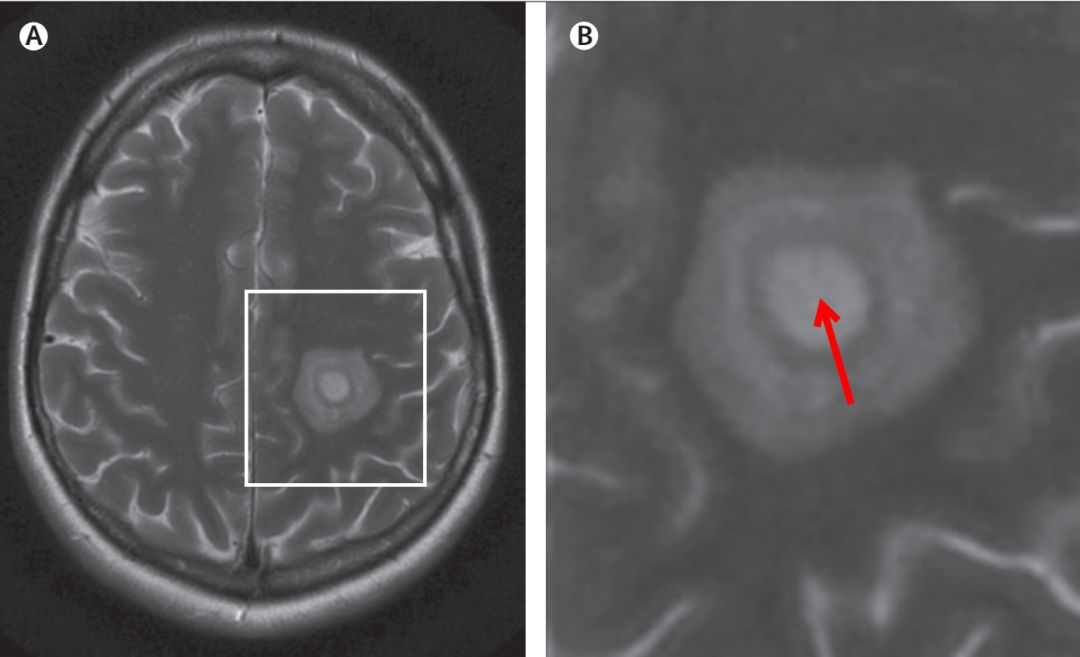

MRI表现:Baló’s 在T1像的特点是多个等、低信号交替的同心圆,在T2加权序列上表现为围绕高信号圆心(风暴眼)的高低信号环,也有其他模式如玫瑰、康乃馨甚至马赛克形状的报道。

再典型一点的如下(红色箭头即风暴眼(storm center)):

最经典的,年轮样改变,数不清多少环长这样:

图自:Lancet Neurol 2014; 13: 740–46